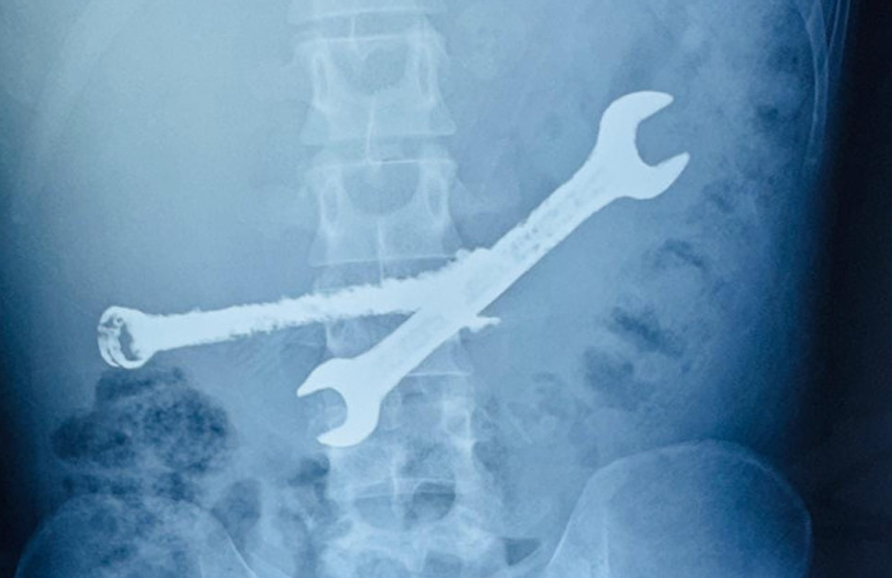

Ultrasound image detecting an iron wrench in the 26-year-old man's abdomen. Photo: *Tanmay Pareek*. |

After more than two hours of intense surgery, the surgical team successfully removed two iron wrenches and seven intact toothbrushes. Dr. Pareek diagnosed the patient with a mild mental disorder, leading to the ingestion of non-food items, a condition known as Pica syndrome. This dangerous habit emerged about one month before hospitalization, with the foreign objects gradually accumulating and causing severe damage to the digestive system.